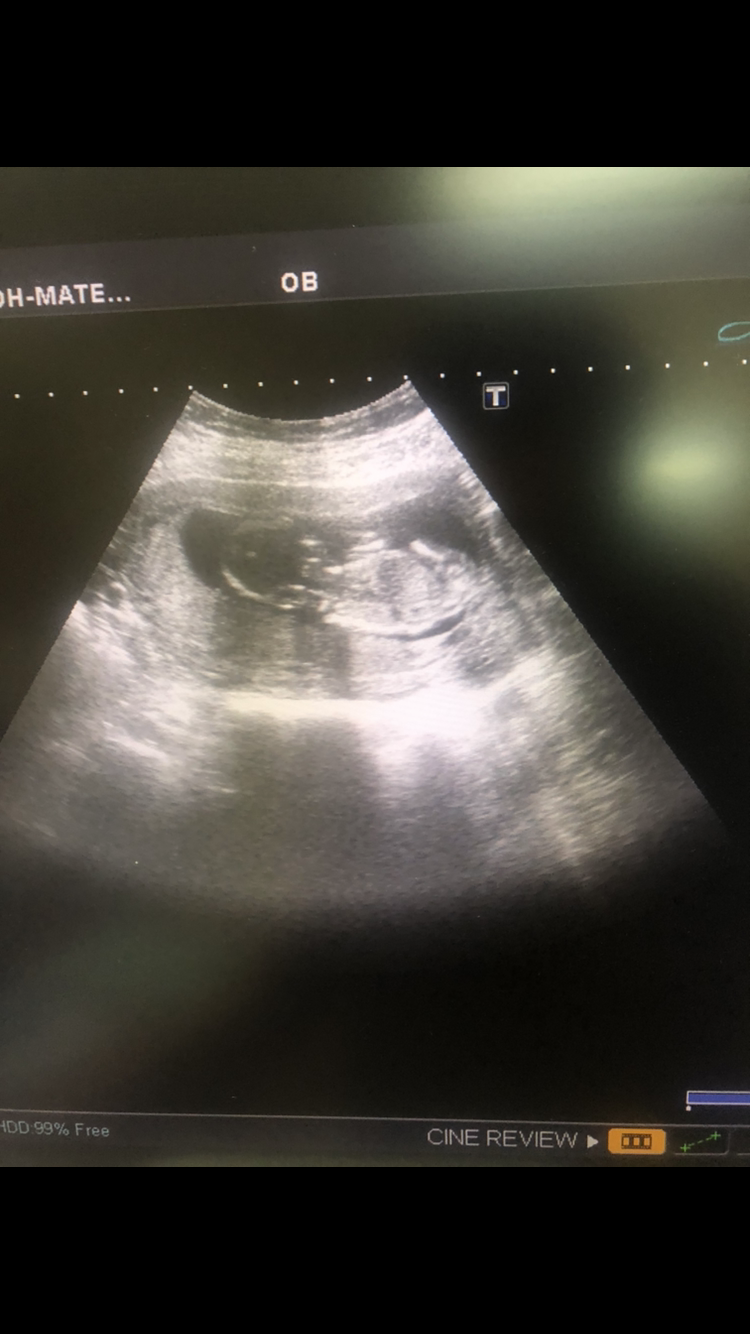

بنات الله يسعدكم شوفو لي السونار وش تتوقعون ادري الصوره مو عند الرجلين بس الرجلين كانت مقفله والبيبي نايم 😅

في بنات يعرفون من نظرريه الناب

والله ماأعرف في نظرية الناب بس اعرف في جنسه لو كانت الصوره واضحه الله يرزقك ماتتمنينهوالله ماأعرف في نظرية الناب بس اعرف في جنسه لو كانت الصوره واضحه الله يرزقك ماتتمنينه